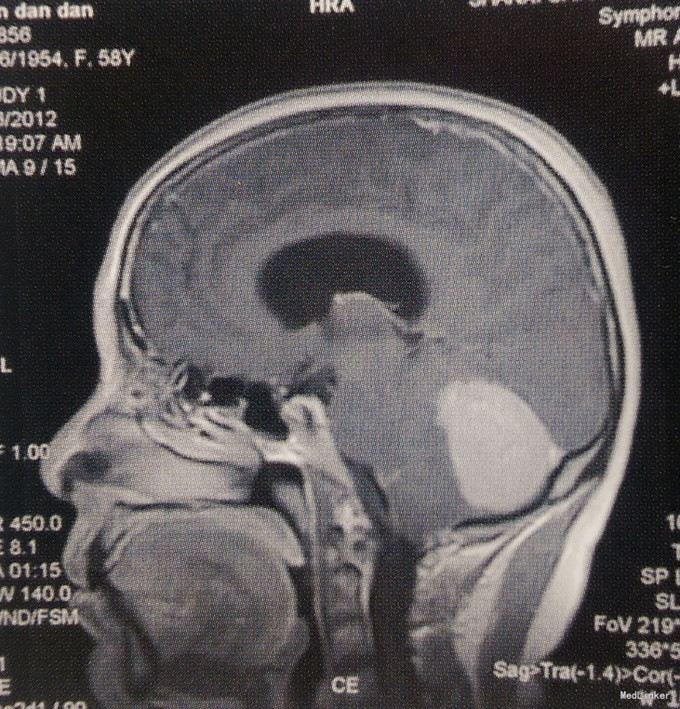

体格检查:神经系统未见阳性体征。 术前影像学检查 头颅MRI检查:小脑幕下两侧小脑半球脑外占位性病变,左侧病变为著,边界清楚,第四脑室受压变窄,幕上脑室轻度积水,增强扫描病变明显均匀强化,考虑脑膜瘤可能性大。